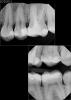

Михалыч007 Опубликовано 24 мая, 2012 Поделиться Опубликовано 24 мая, 2012 ещё одномоментная пломбировка зуба гуттаперчей Ссылка на комментарий